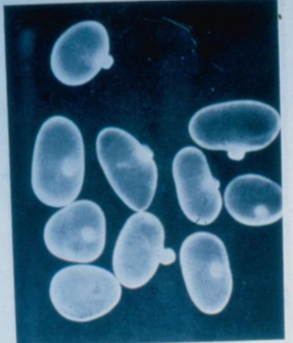

Giardia lamblia (cyst)

knowt flashcard image